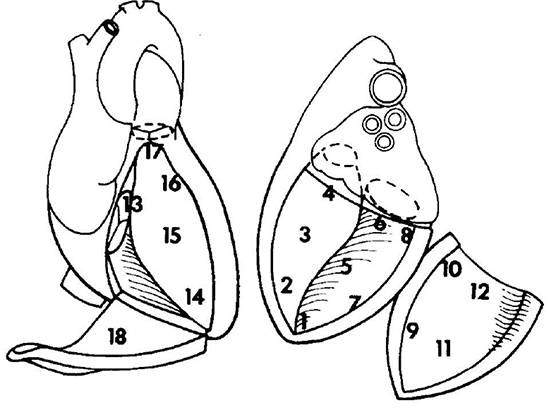

Figure 2 Endocardial Areas of Josephson[13]

Left ventricle: 1 = apex, 2 = apical septum, 3 = mid septum, 4 = basal septum, 5 = inferior, 6 = inferoposterior, 7 = apical low lateral, 8 = inferoposterolateral, 9 = anterolateral, 10 = lateral basal, 11 = midanterior, 12 = superior basal. Right ventricle: 13 = tricuspid annulus/basal septum, 14 = apex, 15 = mid septum, 16 = anterior septum, 17 = outflow tract, 18 = lateral/free wall.